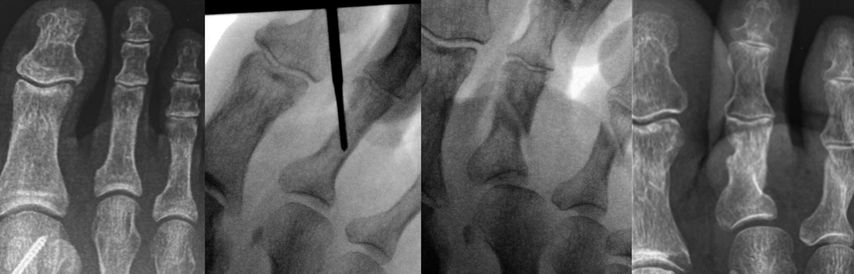

Eine Hammerzehe oder auch mediale bzw. laterale Deviation kann mit perkutan durchgeführten Osteotomien mit der minimalinvasiven Fräse korrigiert werden. Bei einer Hammerzehenfehlstellung erfolgt nach Stichinzision unter der Basis der Grundphalanx bzw. dorsal an der Mittelphalanx, nach Abschieben der Weichteile mittels Elevatorium, mit der Fräse eine Kortikotomie unter Erhaltung der gegenüberliegenden Kortikalis. Dann kann durch Druck die Osteotomie geschlossen und damit die Korrektur erzielt werden. Falls über dem PIP-Gelenk noch eine Prominenz tastbar ist, wird diese über die dorsale Inzision mit der Fräse abgeschliffen.21,22

Isolierte Überlängen von Zehen können mit minimalinvasiven Osteotomien an der Grundphalanx sehr gut korrigiert werden (Abb. 6). Bei Fehlstellungen in der Transversalebene wird ebenfalls über eine Stichinzision in Höhe der Fehlstellung eine Kortikotomie durchgeführt und die Fehlstellung durch Schließen der Osteotomie korrigiert (Abb. 7).

Die Nachbehandlung erfolgt mit Tape-Zügeln im postoperativen Schuh.